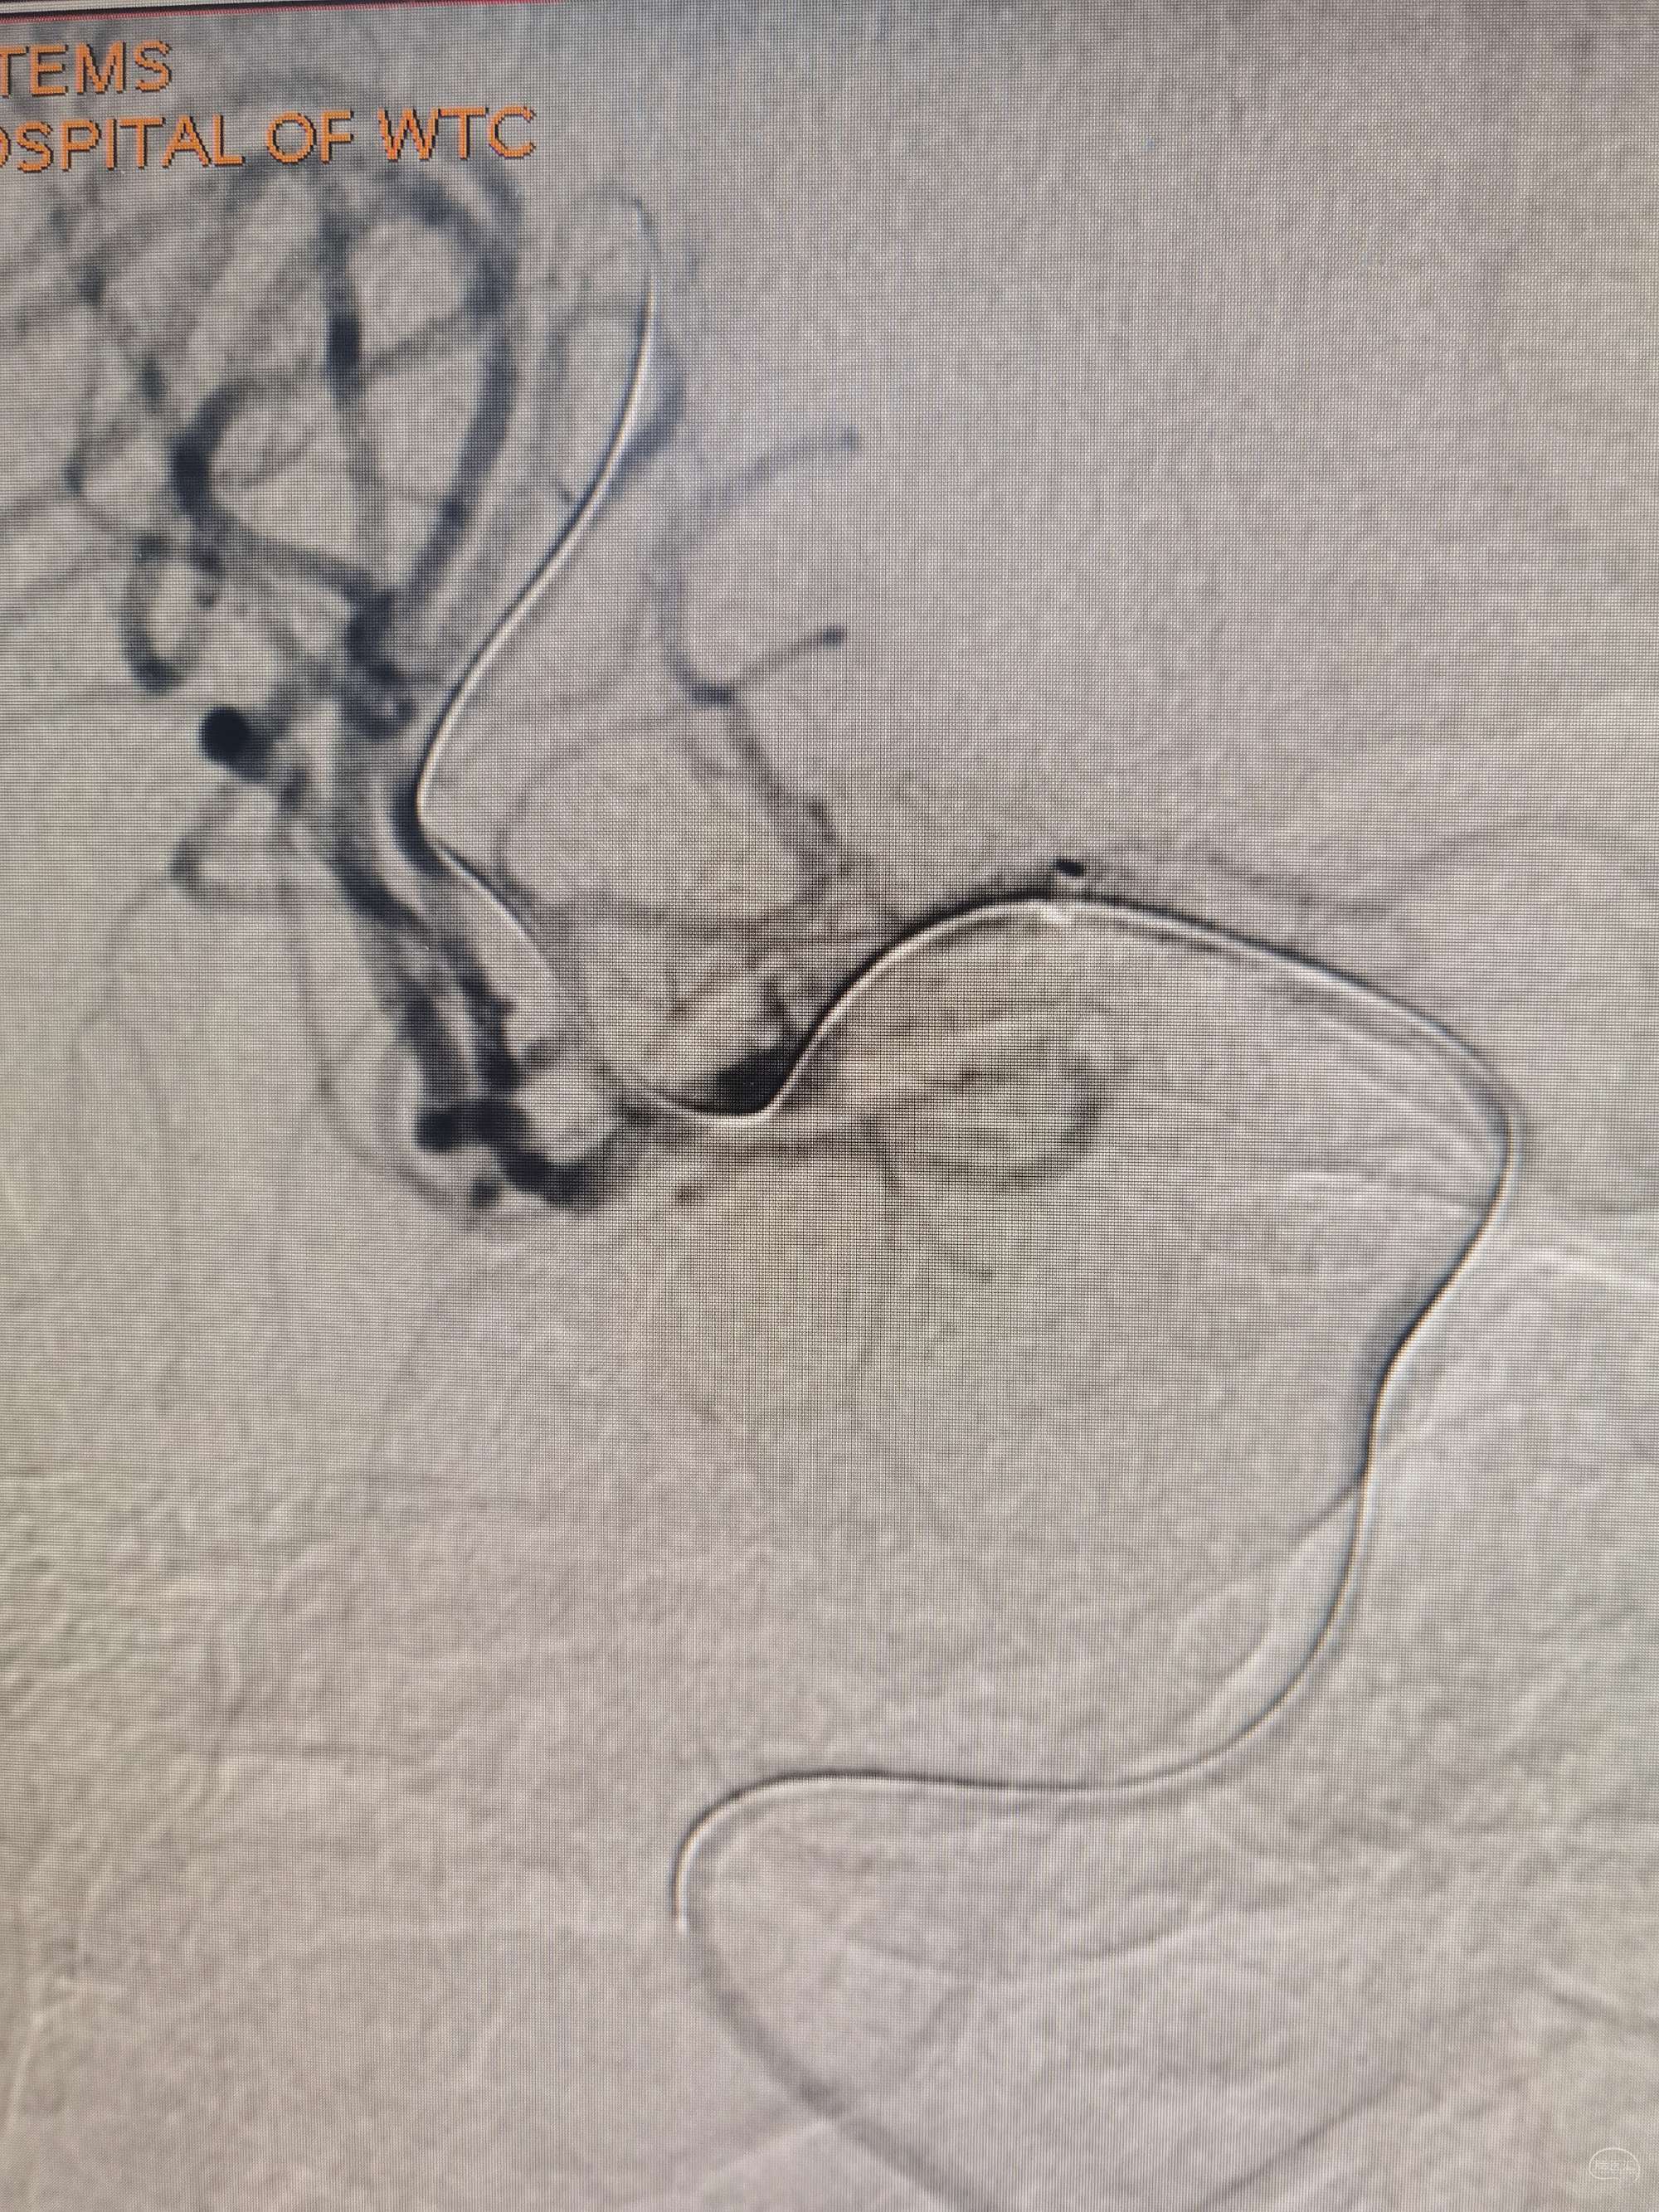

按照开会时候大家商量的办法,至少这例患者不适合啊,在抗板的过程中都肉眼可见的血栓形成。故下一步处置:再上刚才的取栓支架,释放后手推冒烟:

解脱后再次观察10min

术中继续观察10min,远端血流tici3a级。结束手术。